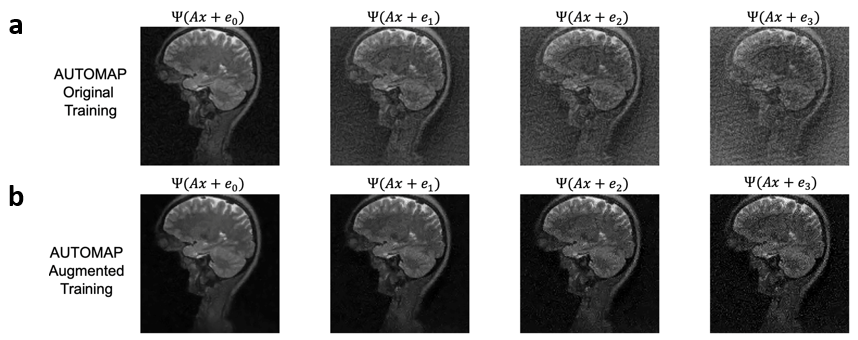

We trained AUTOMAP models to study two properties of training datasets, robustness to FOV artifacts and adversarial noise. The training images were 2D T1-weighted brain MR images acquired at 3 T collected from the MGH-USC Human Connectome Project (HCP) public dataset4. For the FOV experiments, we needed to curate two datasets, one with a single FOV (random samples shown in Fig 1a) and one with multiple FOVs (random samples shown in Fig 1b). Fig 1c was used to showcase artifacts from the different models in Fig 2 and discussed in the results. To study the robustness to adversarial noise and the role of numerical properties of a dataset, the adversarial noise was generated using a gradient ascent with momentum perturbation search algorithm3. The original AUTOMAP was trained to output positive, magnitude images. The adversarial noise pushed this boundary to generate negative and complex-valued noise in the image domain. When applied in the k-space domain, the numerical properties pushed AUTOMAP beyond its reconstruction capabilities leading to artifacts. In Fig 3, we show the adversarial noise is highly structured and contains negative values. Instead of training on positive, magnitude-only images, we added randomized constant offsets (between -0.1 and +0.1) to the training images and retrained AUTOMAP. We show the results of both these models in Fig 4.

The top row in Fig 2 demonstrates what artifacts arise when a model trained on a single FOV is tested on an out-of-distribution FOV in the image domain. All conditions, without noise (Fig 2a), Gaussian noise (Fig 2b), and Poisson noise (Fig 2c), display artifacts (particularly in the dark image background region). After retraining AUTOMAP with multiple FOVs, under both noiseless and noise-applied conditions, the artifacts were significantly reduced (bottom row Fig 2 d-f). We tested and demonstrated how important the role of training data augmentations is through something as simple as incorporating multiple FOVs in the training data. In a clinical setting, these same artifacts could lead to a misdiagnosis or a delay as the clinical practitioners may not be aware where the fault occurred. We also demonstrate the role of the numerical properties of a training dataset and how artifacts introduced by adversarial noise can be avoided. Fig 4a (top row) demonstrates artifacts that arise from adversarial noise. After training a network on images that contain negative offsets due to the adversarial noise consisting of negative values, the retrained AUTOMAP model doesn’t contain the same artifacts in Fig 4b (bottom row). If adversarial noise is a concern, we demonstrate it is important to study the numerical properties of the dataset and augment it appropriately so the model can generalize in practice.

Fig 4: Improved reconstruction in the presence of adversarial noise by augmenting training dataset numerical properties. A) Original AUTOMAP network reconstructing in the presence of adversarial noise samples (top row). B) Retrained AUTOMAP network (adding randomized constant offsets between -0.1 and +0.1 for previously out-of-distribution negative-valued outputs) has significantly fewer artifacts previously caused by the adversarial noise (bottom row).